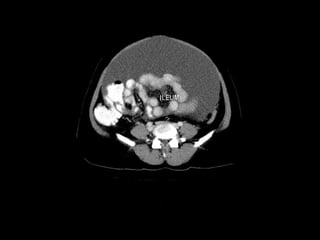

Radiographers use medical imaging equipment like X-rays and MRIs to produce images of patients' internal structures and organs. They are responsible for positioning patients, operating scanning machines, and ensuring quality images. Radiographers must have strong attention to detail, excellent communication skills, and the ability to work well under pressure to accurately capture anatomical features and diagnose any abnormalities.